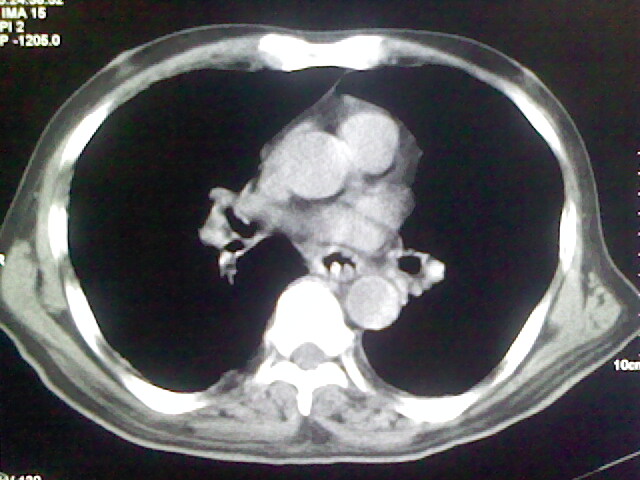

男,70岁,脑出血,长期卧床,左侧背部可触及肿块

背部没见到肿块呀,有感染灶。

肺部感染,背部筋膜增厚,考虑坠积性水肿或炎症

食道里是什么

你放上去的